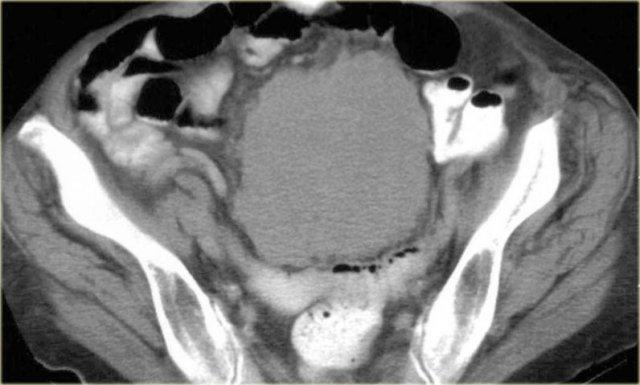

Hình bên trái là bệnh nhân nam 33 tuổi than phiền về tình trạng bụng ngày càng to, cảm giác đầy bụng và sờ thấy khối ở bụng.

Trước tiên hãy nghiên cứu các hình ảnh bên trái rồi tiếp tục xem hình MRI.

Hãy tìm các đặc điểm hình ảnh hữu ích trong chẩn đoán phân biệt.

Trước hết, đây là tổn thương có bờ rõ với giảm tỷ trọng trên CT.

Có ngấm thuốc nhẹ xung quanh tổn thương và một số dải ngấm thuốc nhỏ bên trong tổn thương.

Trên MRI, tổn thương giảm tín hiệu trên chuỗi xung T1W như dự kiến.

Trên chuỗi xung T2W, tổn thương tăng tín hiệu tương đối.

Kết hợp với giảm tỷ trọng trên CT, điều này cho thấy có chứa mucin bên trong tổn thương.

Đặc điểm này rất gợi ý chẩn đoán u xơ mạc treo.